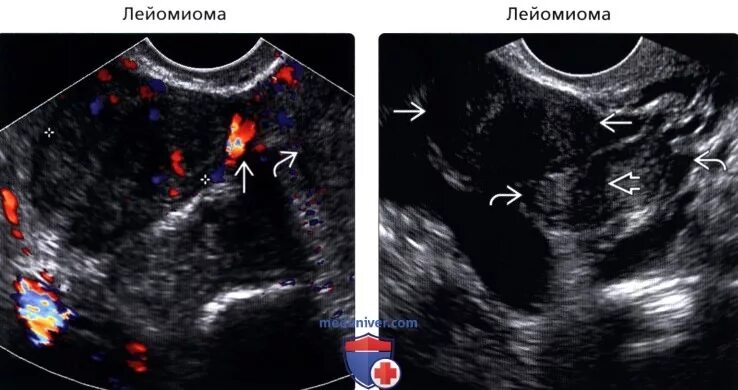

Солидное образование в малом тазу